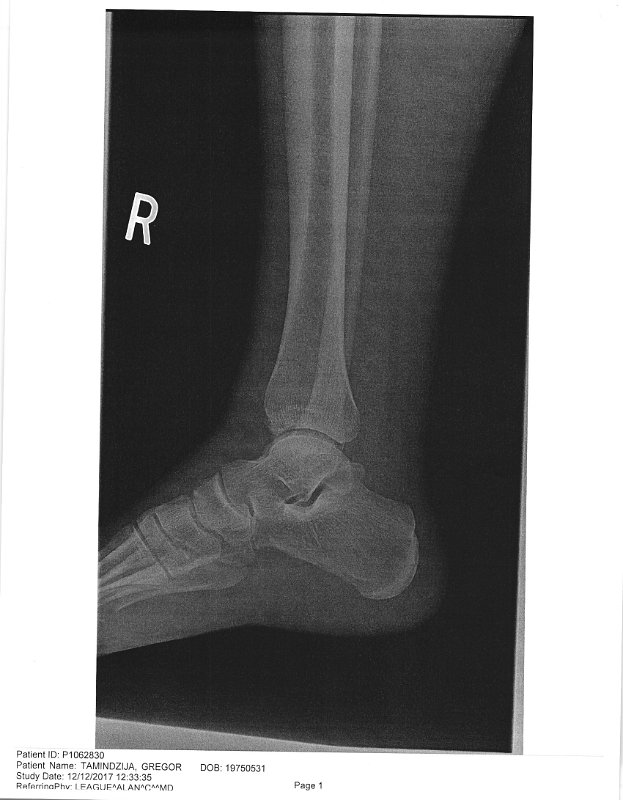

DocFile (2)